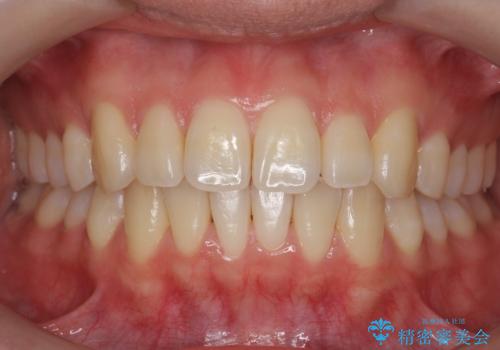

前歯のがたつきをなおしたい マウスピース矯正

担当医 大元洋佑

![[ マウスピース矯正 ] 前歯の角度・がたつきを治したい。の症例 治療前](https://seimitsushinbi.jp/wp/wp-content/uploads/2024/02/IMG_7820-500x350.jpg?v=1707810350)

![[ マウスピース矯正 ] 前歯の角度・がたつきを治したい。の症例 治療後](https://seimitsushinbi.jp/wp/wp-content/uploads/2024/02/8334681fa61954fc45ff8cef14f33166-500x350.jpg?v=1707810480)